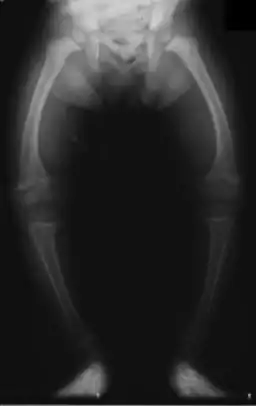

| X-ray of a two-year-old with rickets, with a marked bowing of the femurs and decreased bone density | |

An X-ray or radiograph of an advanced patient with rickets tends to present in a classic way: the bowed legs (outward curve of long bone of the legs) and a deformed chest. Changes in the skull also occur causing a distinctive "square headed" appearance known as "caput quadratum".[14] These deformities persist into adult life if not treated. Long-term consequences include permanent curvatures or disfiguration of the long bones, and a curved back.[15]

- Radiography typically show widening of the zones of provisional calcification of the metaphyses secondary to unmineralized osteoid. Cupping, fraying, and splaying of metaphyses typically appears with growth and continued weight bearing.[41] These changes are seen predominantly at sites of rapid growth, including the proximal humerus, distal radius, distal femur and both the proximal and the distal tibia. Therefore, a skeletal survey for rickets can be accomplished with anteroposterior radiographs of the knees, wrists, and ankles.[41]

Occasionally surgery is needed to correct severe and persistent deformities of the lower limbs, especially around the knees namely genu varum and genu valgum. Surgical correction of rachitic deformities can be achieved through osteotomies or guided growth surgery. Guided growth surgery has almost replaced the use of corrective osteotomies. The functional results of guided growth surgery in children with rickets are satisfactory. While bone osteotomies work through acute/immediate correction of the limb deformity, guided growth works through gradual correction.[7]